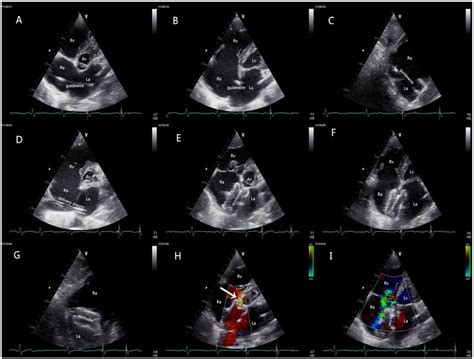

The Echo Transthoracic Complete is a comprehensive diagnostic examination that utilizes high-frequency sound waves to visualize the heart. Unlike invasive procedures, this test is entirely external, meaning the ultrasound probe—or transducer—is moved across the surface of your chest. The sound waves bounce off the heart structures and are converted into moving images on a monitor.

A "complete" study is distinguished from a limited or focused echocardiogram because it involves a thorough evaluation of the heart’s anatomy and hemodynamic performance. It covers several specific aspects of cardiac function:

- Cardiac Morphology: Measurement of the size and thickness of the heart chambers and walls.

- Valve Function: Assessment of the mitral, aortic, tricuspid, and pulmonary valves to ensure they are opening and closing correctly.

- Blood Flow Dynamics: Using Doppler ultrasound to measure the velocity and direction of blood flow through the heart.

- Ejection Fraction: Calculating how much blood the left ventricle pumps out with each contraction, a key indicator of heart health.

- Pericardial Evaluation: Checking for fluid accumulation in the sac surrounding the heart.